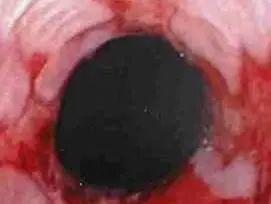

左右滑动查看胃酸侵蚀食道

如果这个「阀门」出现了问题,胃酸就会反流而上,刺激食道,造成食道有烧灼的感觉,时间过长就会引起食道壁的灼伤,引发食管炎。

而当胃酸突破咽喉防线,还会使敏感的呼吸道灼伤,于是咳嗽、咽喉异物感等呼吸道症状也会随之而来。

胃食管反流病长期发作,有可能出现巴雷特食管并发症的可能。巴雷特食管是食管腺癌的癌前病变。

食道癌变